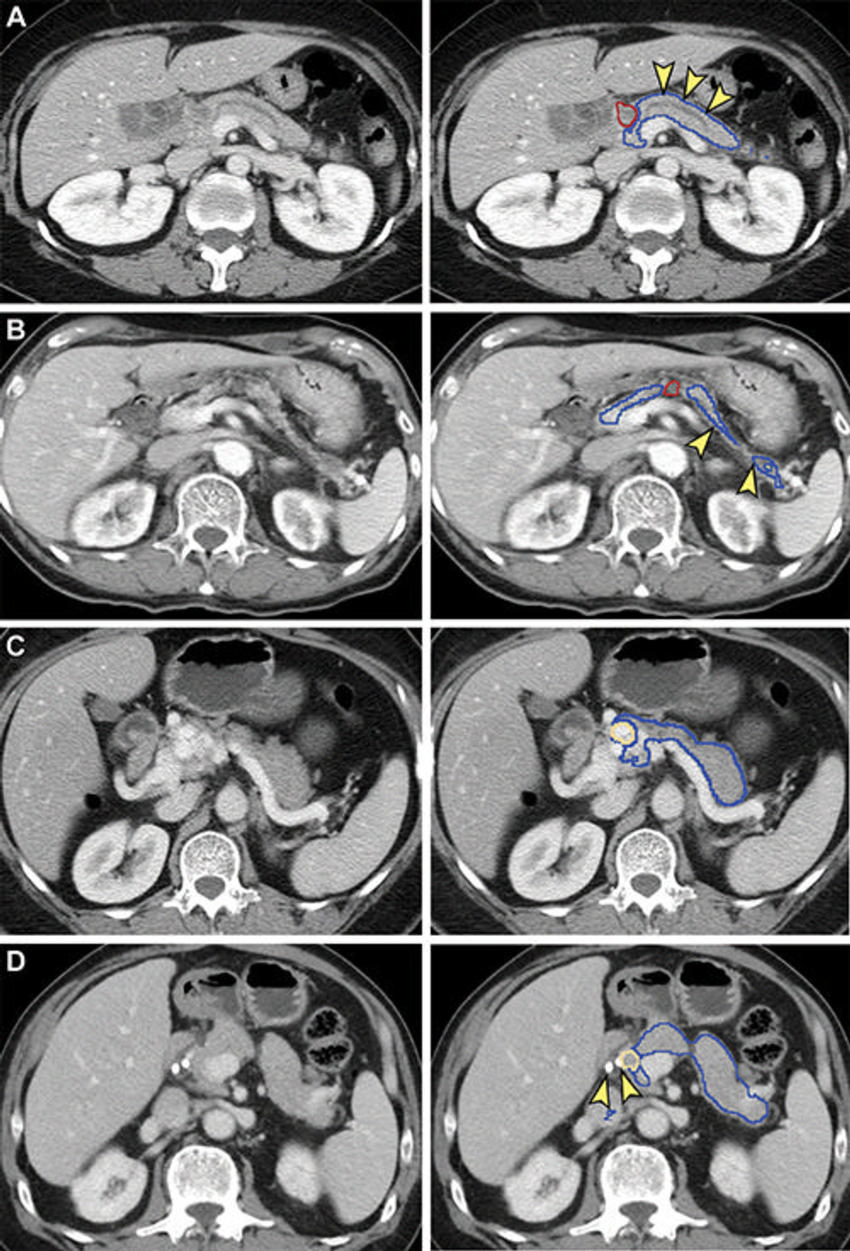

Figure 3. Receiver operating characteristic curves of the classification models in the (A) training and validation set, (B) local test set, and (C) nationwide test set. CNN = convolutional neural network. Representative CT scans (left column) with tumor at the pancreas (D) head, (E) body, and (F) tail show correspondence in tumor location between manual segmentation by radiologists (middle column) and predictions by the segmentation model (right column). Blue outline indicates the pancreas; yellow outline indicates tumor.

High-res (TIF) version

Figure 4. False-negative (A, B) and false-positive (C, D) tumor segmentation by the segmentation model. Blue and yellow outlines indicate normal pancreas and tumor segmented with the segmentation model, respectively. Images in the left column are original unannotated CT scans. (A, B) Tumors (red outline) were not segmented by the segmentation convolutional neural network. The upstream pancreas shows secondary signs of pancreatic cancer, including dilation of the pancreatic duct with abrupt cutoff (arrowhead in A) and parenchymal atrophy with dilation of the pancreatic duct (arrowhead in B). (C) Collateral veins secondary to idiopathic portal vein thrombosis were incorrectly segmented as tumor by the segmentation model. (D) Pancreatic parenchyma adjacent to biliary stents (arrowhead) placed for relieving obstructive jaundice from hepatocellular carcinoma was incorrectly segmented as tumor by the segmentation model.